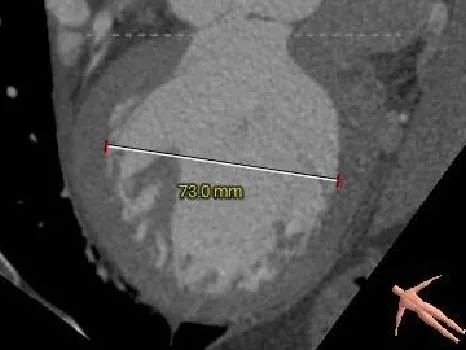

左室测量

舒张期大左室,典型关闭不全引起的心室扩张